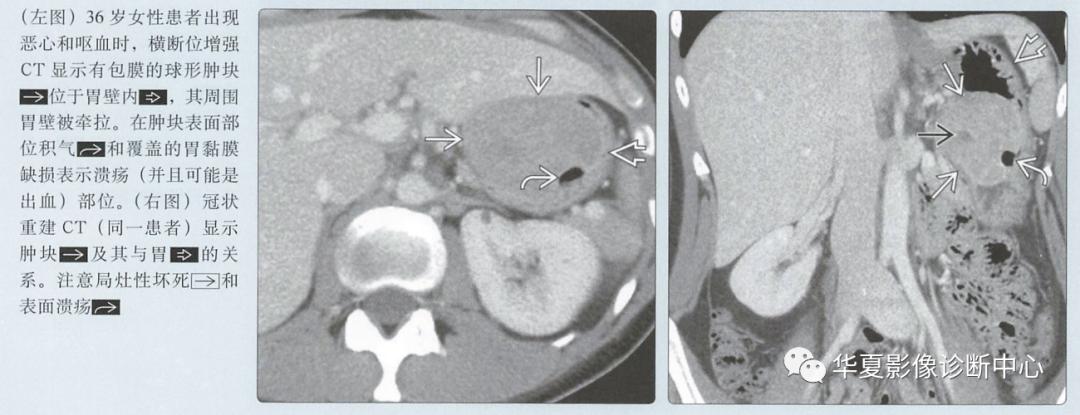

溃疡在较大的肿块中很常见

增强CT

动脉期图像呈低或高血供,边界清楚的黏膜下肿块;溃疡和坏死是常见的

恶心、呕吐、体重减轻

心当胃表面和GIST溃烂时, 消化道出血